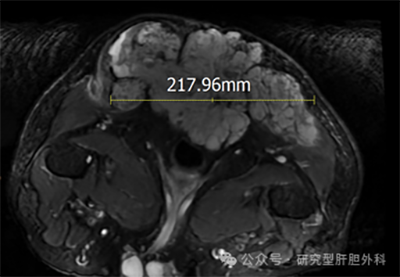

核磁报告:骶尾部骨质破坏消失,肿瘤上下范围约17cm,深度14cm,向两侧累积臀部肌肉,上界至骶2水平,向前至直肠后壁。髂骨、双侧股骨头、右股骨干、腰4、腰5椎体多发转移。同时患者考虑合并肝、肺等多处转移。

术前核磁图像